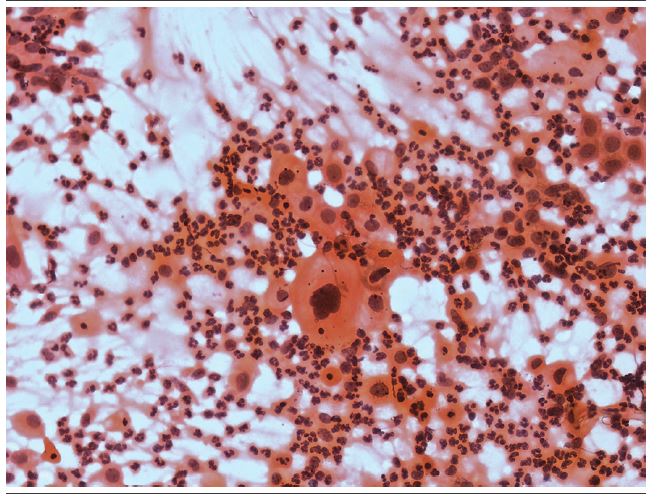

From the total of 20 abnormal cases (4%) of samples evaluated (Figures 1 and 2), four (20%) took hormones: two cases were classified as atypical squamous cells - cannot exclude high-grade squamous intraepithelial lesion [(ASC-H) - 10%], and two as atypical squamous cells of undetermined significance [(ASC-US) - 10%]. There was no statistically significant difference between the lesion degrees and the age of the patients (Table 2).

Studies have shown that smears with the presence of endocervical cells have a significantly higher frequency of detected abnormalities compared to those with a lack of such cells, since it is in SCJ that most of the precursor lesions of cervical cancer originate. The presence of an endocervical component, therefore, guarantees an appropriate sample of this region, increasing the probability of detecting cervical abnormalities(17-19). The presence of endocervical cells in the sample is important mainly for the detection of endocervical adenocarcinomas cases, which, although less frequent, may also occur, especially in women older than 50 years(17,20). Our results confirm these studies, since the two cases of adenocarcinoma in situ (ACI) reported in the present study could not be identified if no SCJ cells were present.

When associated with vaginitis, the identification of alterations in the atrophic epithelium presents diagnostic difficulties, since parabasal cells can degenerate, resulting in a pattern of autolysis, resembling tumor cells. The granular material at the background of the slide resulting from this degeneration may also be mistaken for tumor diathesis(8,12).